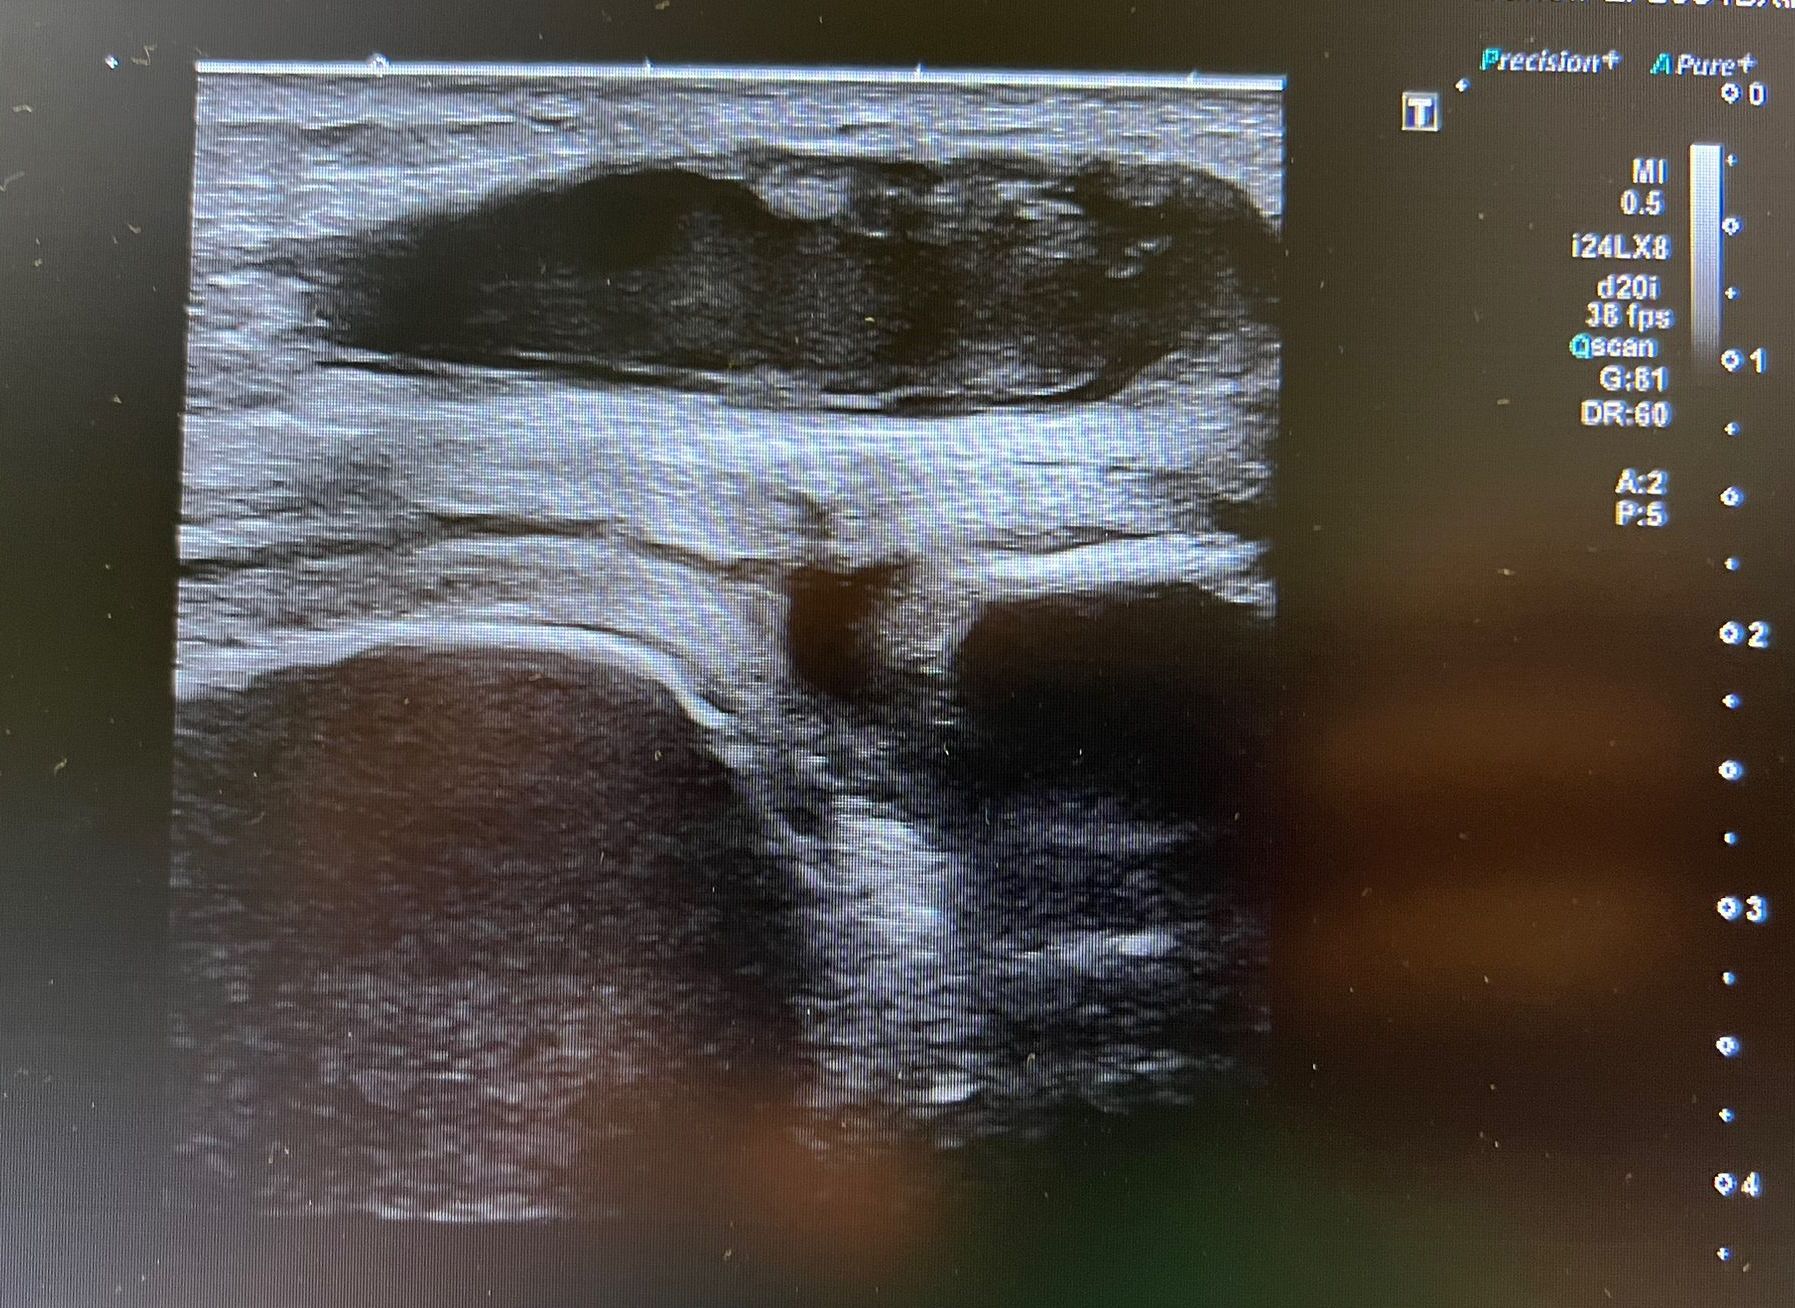

Hallazgos ecográficos

Se realiza ecografía clínica en la que se aprecia colección heterogénea en bursa prerrotuliana así como edema de partes blandas. No aumento de líquido ni colecciones a nivel intraarticular sugestivas de artritis séptica.

• Se realiza punción de la bursa ecogiada para cultivo de la colección.